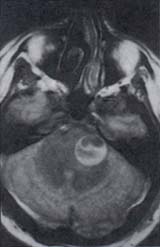

Figura 15. Infartos pontinos